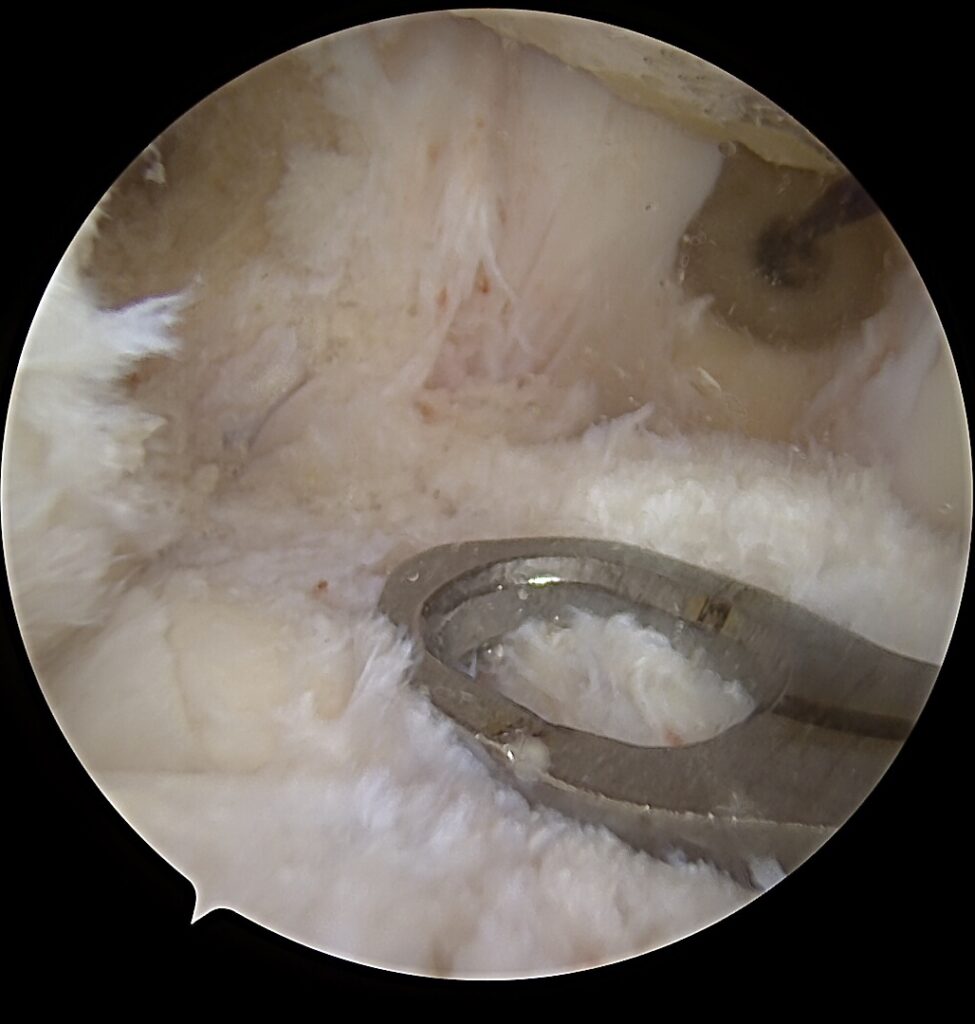

Kodėl V formos rekonstrukcija?

anatomiškai atkuria dvi funkcines kelio stabilumo kryptis

✔️ geriau paskirsto apkrovas

✔️ mažina likutinio nestabilumo riziką